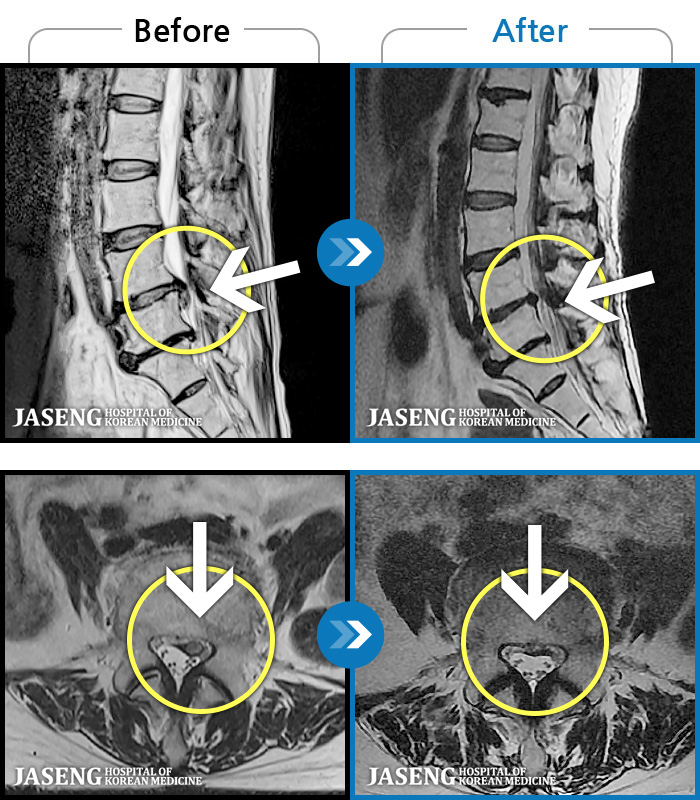

MRI ġ

1,237 MRI ũ ʸ Ȯϼ.

㸮 ϻ .